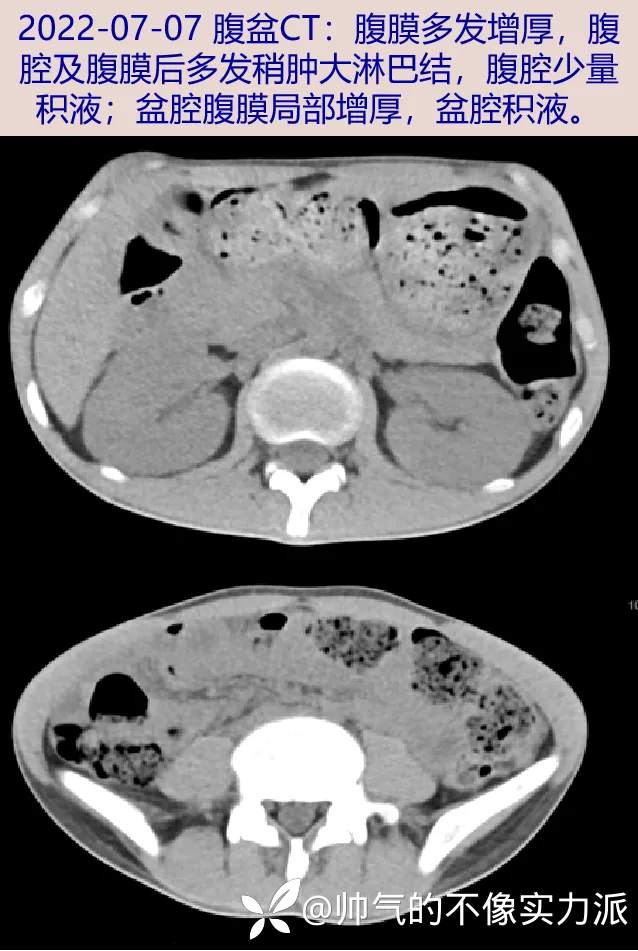

- 2022-07-07 随访腹盆CT:腹膜多发增厚,腹腔及腹膜后多发稍肿大淋巴结,腹腔少量积液;盆腔腹膜局部增厚,盆腔积液。